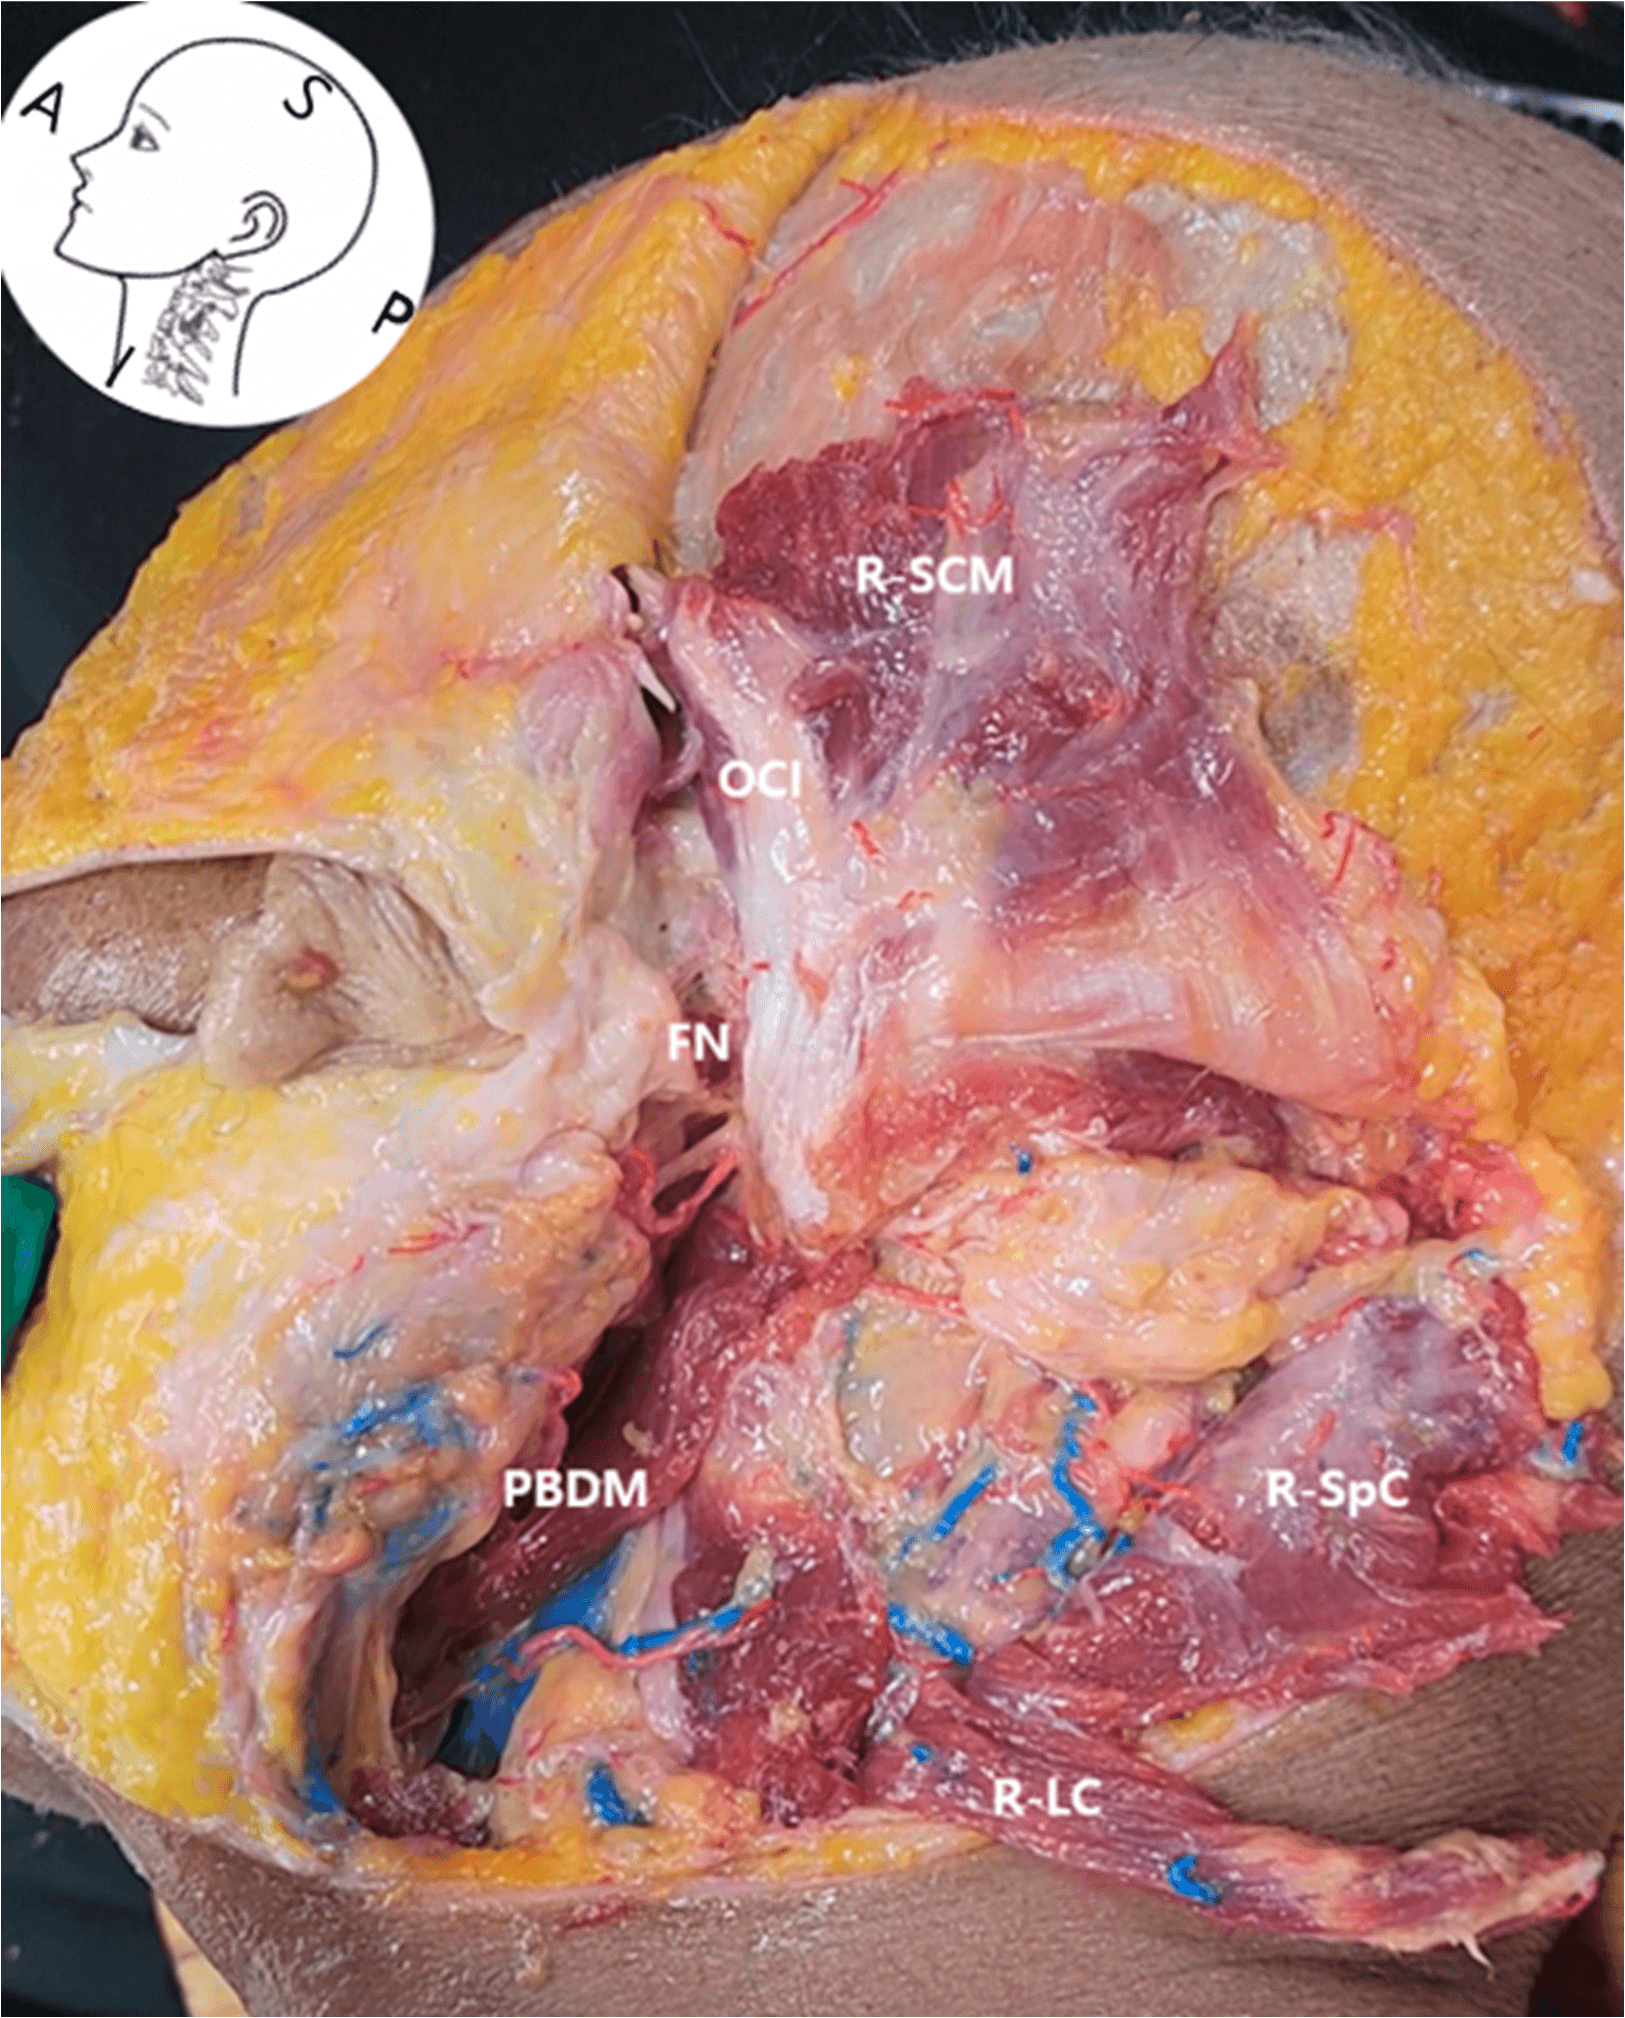

안면마비 - Layer-by-layer dissection of the right lateral neck showing key anatomical struc Figure 3. Layer-by-layer dissection of the right lateral neck showing key anatomical structures for ultrasound-guided FN access. FN , facial nerve; PBDM , posterior belly of the digastric muscle; R- SCM , reflected sternocleidomastoid muscle; R-SpC , reflected splenius capitis muscle; R-LC , reflected longissimus capitis muscle; OCI , obliquus capitis inferior muscle.